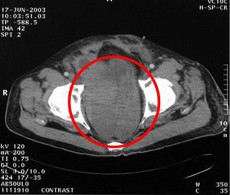

患者病情:左下腹壁脂肪肉瘤2次术后复发,疗前132.9cm2。治疗方案:瘤内注射今又生1-2×1012VP/次/周×14;热疗40MHz 42-43°C,1次/周×22,今又生注射后 3天进行;放疗60Gy结果:疗后肿瘤大小无改变,但50%以上低密度区(LDA),治疗后3周,8kg肿块切除,随访50个月健康生存。

治疗前

治疗后